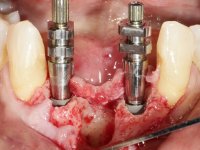

Após estudo imagiológico foi planificada a colocação de dois implantes de 3.3 mm de diâmetro e 10 mm de comprimento. No dia da cirurgia foram extraídos os dentes 42 e 32 e removido o implante. Os implantes foram colocados na zona dos alvéolos tendo o cuidado de lingualizar um pouco o seu posicionamento. Foi feita uma impressão pela técnica de moldeira aberta com o retalho aberto para a confeção da ponte provisória imediata. Enquanto a impressão foi para o laboratório, foram colocados parafusos de cicatrização altos e feita a sutura da ferida cirúrgica. A paciente esperou 2 horas na sala de espera enquanto no laboratório era confecionada a ponte provisória. A ponte provisória imediata aparafusada foi colocada e o seu assentamento controlado imagiologicmente. Passados 3 meses foi realizada a impressão definitiva com uma técnica de moldeira aberta. Nessa consulta aproveitamos para polir a ponte provisória com taças de borracha para que os tecidos moles pudessem maturar em melhores condições. Foi feita a recolha de informação para caracterizar da melhor forma a estrutura monolítica em Zr. Foram utilizadas guias de cor para a cerâmica de tonalidade coronária e gengival. No laboratório foi confecionada uma ponte em Zr. aparafusada que foi cuidadosamente caracterizada. Após aprovação pela paciente foi colocada definitivamente em boca. O aperto foi feito com uma chave dinâmica com 35 N de torque. Os orifícios foram tapados com teflon e obturados com resina composta.